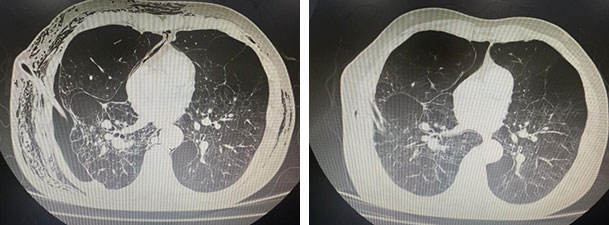

治疗前后CT对比

经过术后精心的护理和康复训练,功夫不负有心人,2月22日,伴随李大爷4个月的引流管终于被顺利拔除。李大爷脸上重新绽放出久违的笑容,家属们也满含热泪,向整个胸外科团队表达了无尽的感激之情。这次成功不仅为李大爷带来了新生,也为医院在老年难治性气胸治疗领域积累了宝贵经验,激励着团队继续在医学道路上砥砺前行,攻克更多难题,为更多患者带去希望。